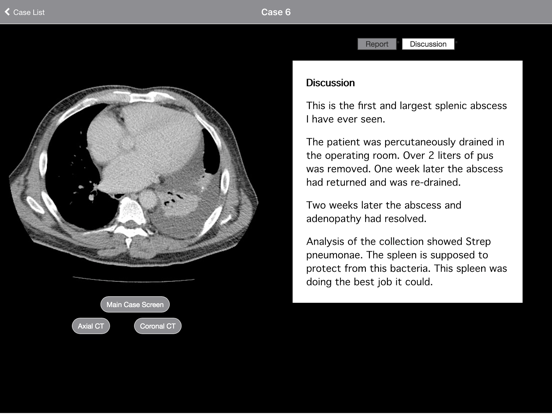

With its 2010 release, "Radiology 2.0: One Night in the ED" became the first radiology teaching file to simulate reading scans at a PACS workstation. The third installment has now arrived. Volume 3. Cases from the End of the World In 2015 I left a large, tertiary, university, hospital in the United States to practice in a rural town on the East Cape of the North Island of New Zealand. To paraphrase All Black great Richie McCaw, "We are just a small little hospital, in a small little town, in a small little country at the end of the world."   The purpose of this app is to share some of the interesting cases I saw in my first year in my new home.  Disease often presents late to rural hospitals and the scans can be very interesting. Indeed, out here the most common presentation of colon cancer is a CT scan showing large bowel obstruction. However, the cases in this collection are instead unusual or uncommon pathologies. You will be amazed that a region of only 45,000 people has such interesting disease! This teaching file presents 42 interesting cases from my hospital in a small town in New Zealand. The cases are challenging, interesting, and fun. Want to know what kind of pathology lurks at the End of the World? Look no further. Each case is presented as a complete CT or MRI scan that you can scroll through as if at a PACS workstation. Multiple sequences in multiple planes are presented for every case. Report, short discussions, and pathology/clinical followup are presented for each case. The interface incorporates image zoom and pan. In addition, both portrait and landscape orientations are supported. This intuitive teaching file is designed for practicing radiologists who want to see some interesting cases. The extensive content is contained within the app for offline viewing. You can learn radiology on-the-go and in the palm of your hand, even with a few minutes of spare time throughout the day. It is completely free and provided as a resource for medical education. No in app purchases. No subscription fees. Additional: - Dr. Daniel Cornfeld is a consultant radiologist at Haoura Tairawhiti in Gisborne, New Zealand. Prior to that he was an Associate Professor of Diagnostic Radiology at Yale University School of Medicine. The narratives contain his opinions (based on the medical literature) and reflect the way he would teach if you were one of his students. The information in this app does NOT constitute medical advice and is meant to compliment and augment, not replace, pre- or co-existing medical education. Neither Haoura Tairawhiti nor Yale University School of Medicine have officially endorsed this content.